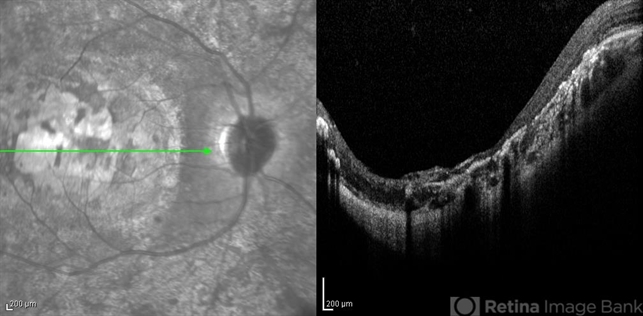

- infrared image, optical coherence tomography (OCT), macular coloboma

- Infrared and OCT images of the right eye of a 25-year-old woman with bilateral macular colobomata and pigmentary retinopathy similar to Leber's congenital amaurosis.